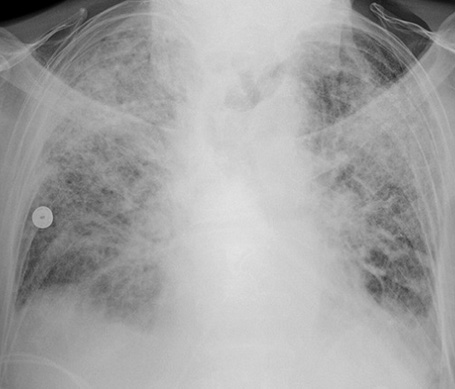

(一)肺水肿的产生 各种致病因素使肺血流灌注不足,直接损害肺泡、毛细血管上皮,引起肺泡毛细血管膜的通透性增加。血循环中的粒细胞、血小板及组织巨噬细胞释放的各种炎症介质将加重上述损害。液体及蛋白质等漏出血管外,导致肺水肿形成,影响通气/灌注比率,导致低氧血症。

(二)肺微小血管杜塞 休克时毛细血管血流缓慢,血液戳滞度增加,易引起微循环血小板、白细胞和红细胞聚集,加上酸中毒等因素可导致dic及肺微小血管血栓形成。在严重感染,创伤情况下亦可见到类似变化。肺微血栓形成后阻塞微循环,使毛细血管内皮细胞及肺泡上皮细胞受损,导致急性呼吸窘迫综合征形成。创伤时可造成肺血管脂肪栓塞,脂肪被肺产生的脂酶溶解,分解产物脂肪酸可损害毛细血管内皮,减少肺泡表面活性物质,导致急性呼吸窘迫综合征。

(三)肺表面活性物质减少 肺表面活性物质衬附在肺泡表面.具有降低肺泡表面张力,瞅肺泡顺应性,稳定肺泡内压,防止肺毛细血管内液体渗入肺泡内的功能。它由厦型肺泡上皮细胞的线粒体合成及分泌的,其主要成分为二棕悯酮亚磷脂,大约18—24小时更新一次。 急性呼吸窘迫综合征发病时,由于上述肺小血管痉挛及肺微小血管栓塞所致的肺血流减少,影响h型肺泡上皮细胞代谢,磷脂合成发生障碍;或由于水肿液、脂肪酸、氧个毒等因素直接破坏作用,使肺表面活性物质减少,表面张力增高,肺泡缩小、陷闭,形成肺不张,同时肺毛细血管内液体渗入肺间质及肺泡。